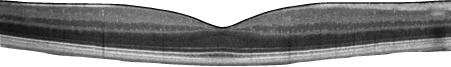

Рисунок 1. ОКТ-изображение здоровой макулы

Точно изучить глазное дно можно только через расширенный зрачок. Для его расширения применяют специальные глазные капли, которые на время делают зрение нечетким. При необходимости делаются также цветные фотографии глазного дна, чтобы можно было отслеживать происходящие изменения. Для диагностики повреждения желтого пятна проводится оптическая когерентная томография (ОКТ) этого участка. Проверку глаз проводит прошедшая специальное обучение медицинская сестра, оптометрист или офтальмолог.